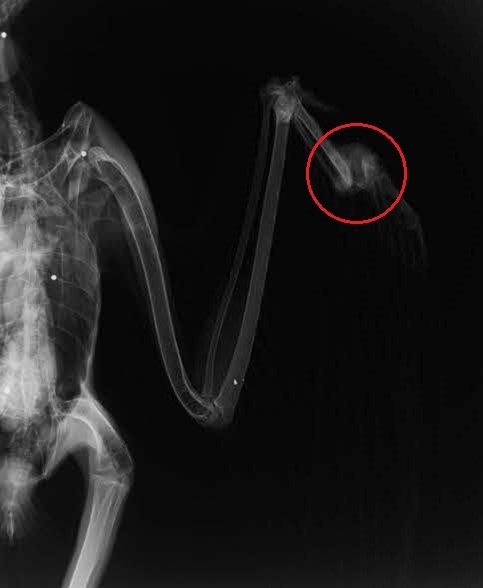

- レントゲン撮影において、骨折の他に、過去に被弾したと推測される合計10発の散弾を確認。

- 散弾は頸部から左脚にかけて確認され、その状態から、比較的近距離で正面方向から射撃された可能性が推測される。

写真:オジロワシのレントゲン写真(猛禽類医学研究所提供)

(白い点として映っているのが散弾。右側写真の赤丸が骨折部位)